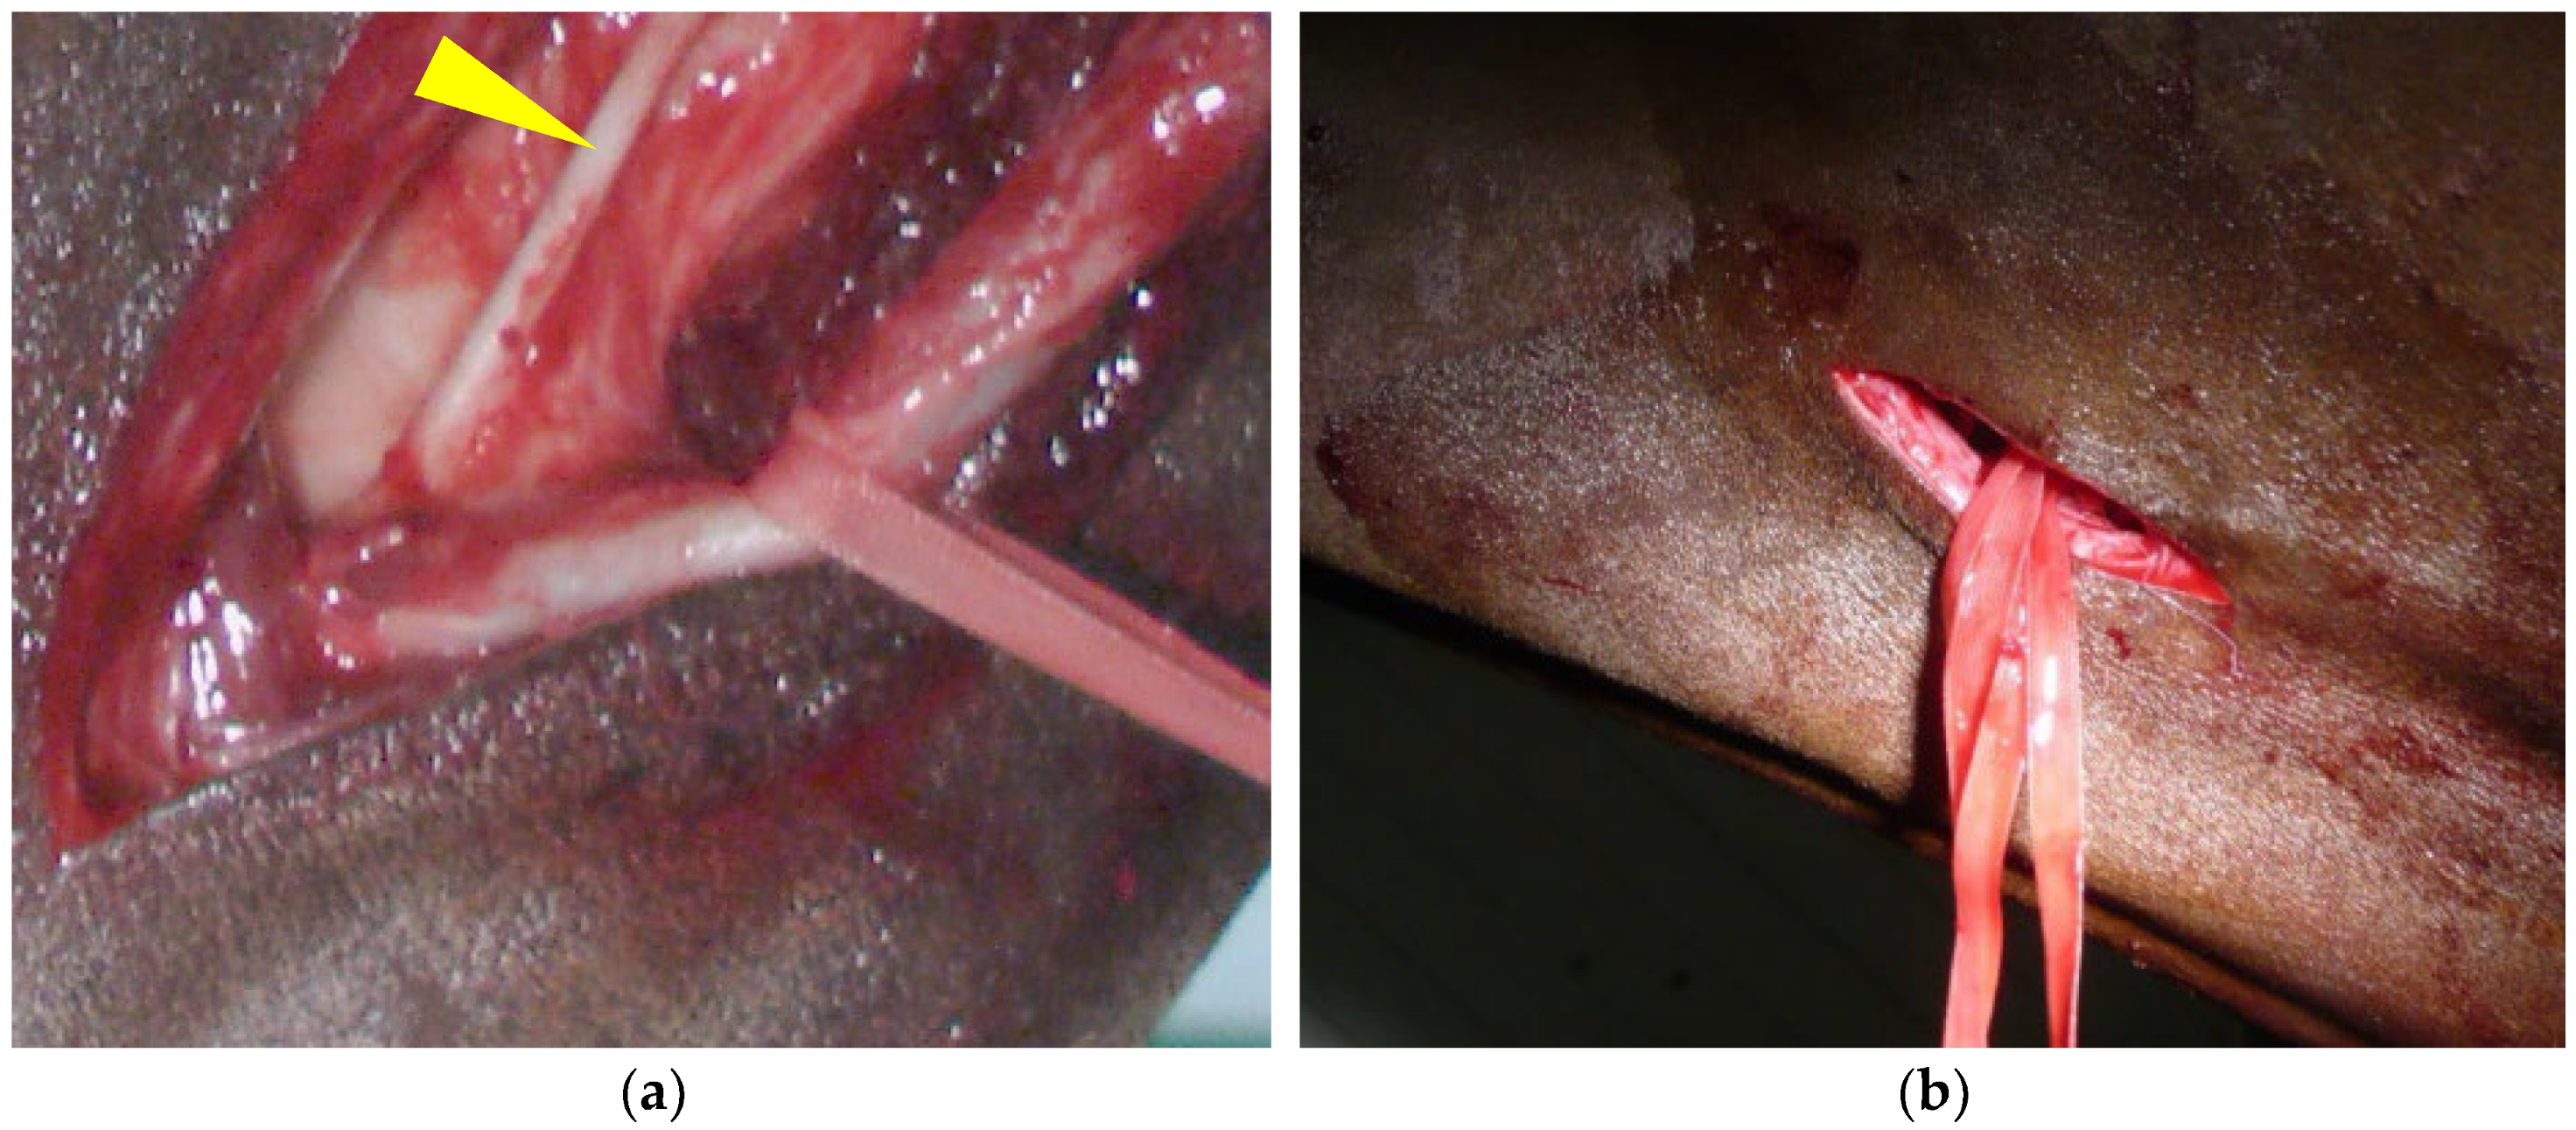

2.2. Step 1: Common Carotid Artery Temporary Ligature